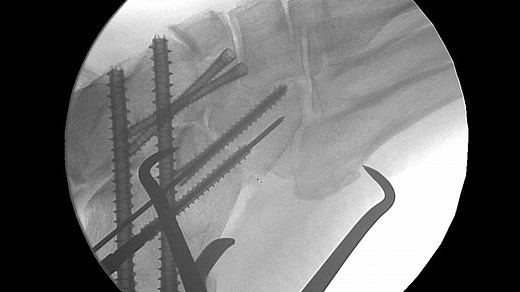

Acutrak 2® Triple Arthrodesis Cadaveric Surgery with Dr Abidi

已浏览 4639 次

2 周前

Vimeo

Acumed LLC